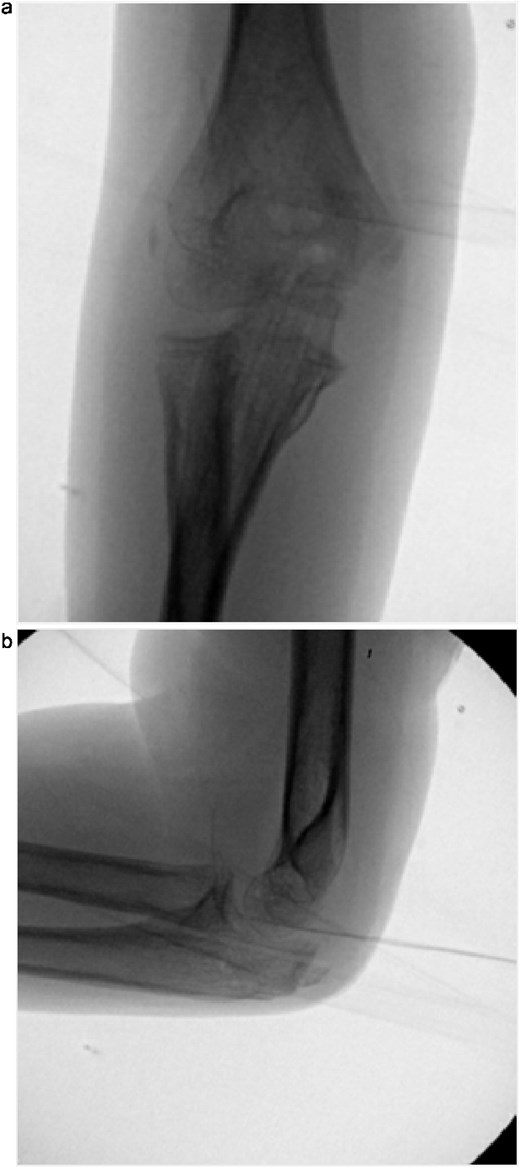

The cast was removed at 5 weeks, and radiographs confirmed maintained alignment (Fig. 4a and b), allowing the patient to transition to a hinged elbow brace. Four months after surgery, she underwent planned removal of the Kirschner wires and tension band (Fig. 5a and b). At 6 months, elbow range of motion was 10°–130° on the right, compared to 0°–140° on the left, and she reported no pain with activities. She was subsequently lost to follow-up.

(a, b) Radiographs at 5 weeks, showing maintained alignment at the time of cast removal.